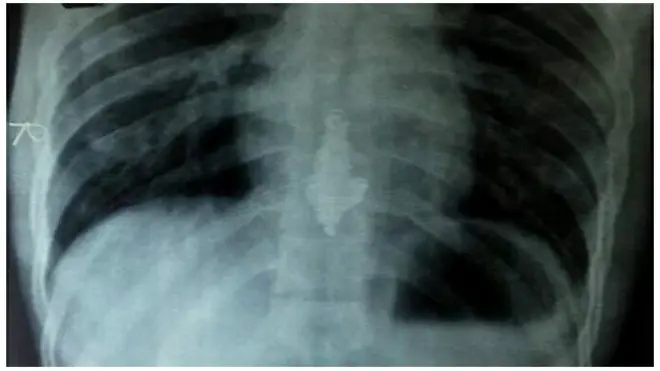

Para petugas bea cukai di Sri Lanka menangkap seorang pria yang mereka katakan mencoba menyelundupkan emas batangan dengan memasukkannya ke anus.

Setelah diperiksa ditemukan emas batangan seberat sekitar 400 gram dengan nilai jual US$14.000 atau setara Rp191 juta.